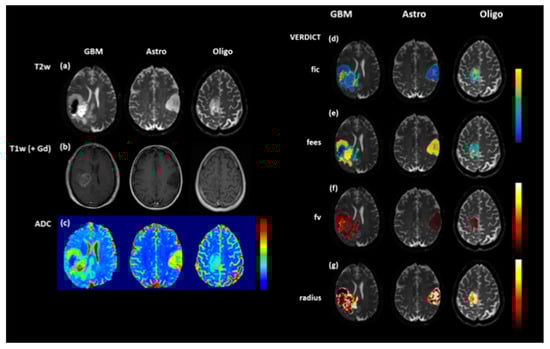

One caveat to the application of DWI for identifying non-enhancing tumour is that lower ADC values do not always correlate with increasing tumour infiltration. Low and persistent diffusion restriction can be associated with non-viable tissue necrosis. In adults, these lesions tend to be periventricular, slowly change over several months and are thought to be a type of treatment toxicity, associated with better outcomes. Novel diffusion modelling techniques such as Vascular, Extracellular, and Restricted Diffusion for Cytometry in Tumours (VERDICT) have been developed at our institution that aim to identify diffusion parameters that more accurately reflect tumour microstructure [53] and will be applied to paediatric brain tumours (Figure 2).

Figure 2.

T2-weighted (T2W (a), T1-weighted (T1W) post contrast (b) and ADC maps (c) in a range of brain tumours: glioblastoma multiforme (GBM), diffuse astrocytoma (Astro) and oligodendroglioma (Oligo). Although the ADC map for the oligodendroglioma (c) is relatively uniform, the Vascular, Extracellular, and Restricted Diffusion for Cytometry in Tumours (VERDICT) parameter map fic (intracellular fraction) (d) demonstrates increased signal at the anterior margin, thought to be a marker of increased cell density. The other VERDICT parameter maps (e) fees (extracellular, extravascular fraction), (f), fv (vascular fraction) and (g) radius (cell radius) also demonstrate tumour heterogeneity which could potentially be used to guide biopsy.